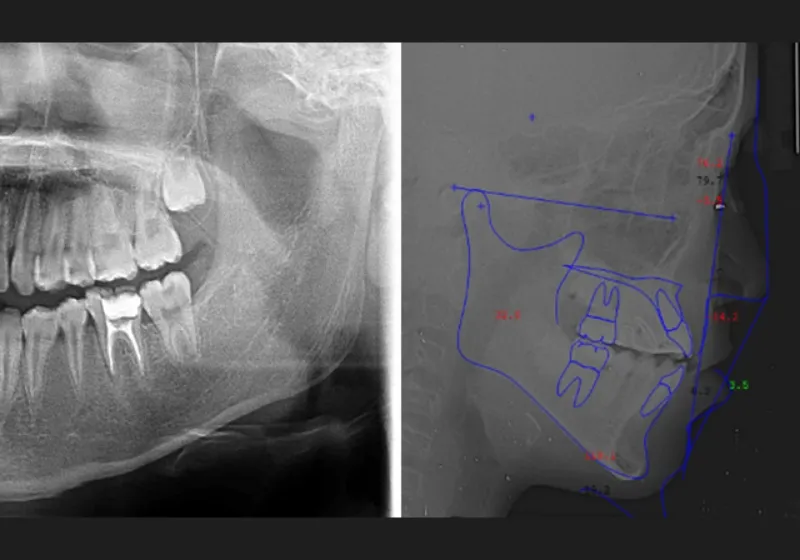

診断のために精密検査を実施します。3Dスキャナーでの歯型取りや顔貌や口腔内の写真撮影、パノラマレントゲンやセファログラムの撮影などで歯列や顎、噛み合わせの状態を詳しく調べます。

WINシステムの装置を作製するには、3Dスキャナーや歯科CTを使用して、患者さまの歯や口腔内の状態を3Dデータとして取得します。このデータを基に、患者さまの口の3Dモデルを作製し、治療シミュレーションを行ないます。シミュレーション結果を患者さまにお見せすることで、治療の流れや最終的な仕上がりを視覚的にイメージできるようになります。このように治療過程を理解することで、患者さまの不安が軽減され、安心して治療に臨むことができます。

3Dメタルプリント矯正装置は、CAD/CAM技術を応用して設計および作製された、優れた適合性と強度をもつ矯正装置です。この装置に矯正用アンカースクリューを連結して固定すると、動かしにくい犬歯、小臼歯、大臼歯を歯根ごと後方に移動させることができます。舌側矯正(裏側矯正)と併用すると、より効果的に歯を移動できるため、治療できる症例の幅が広がります。